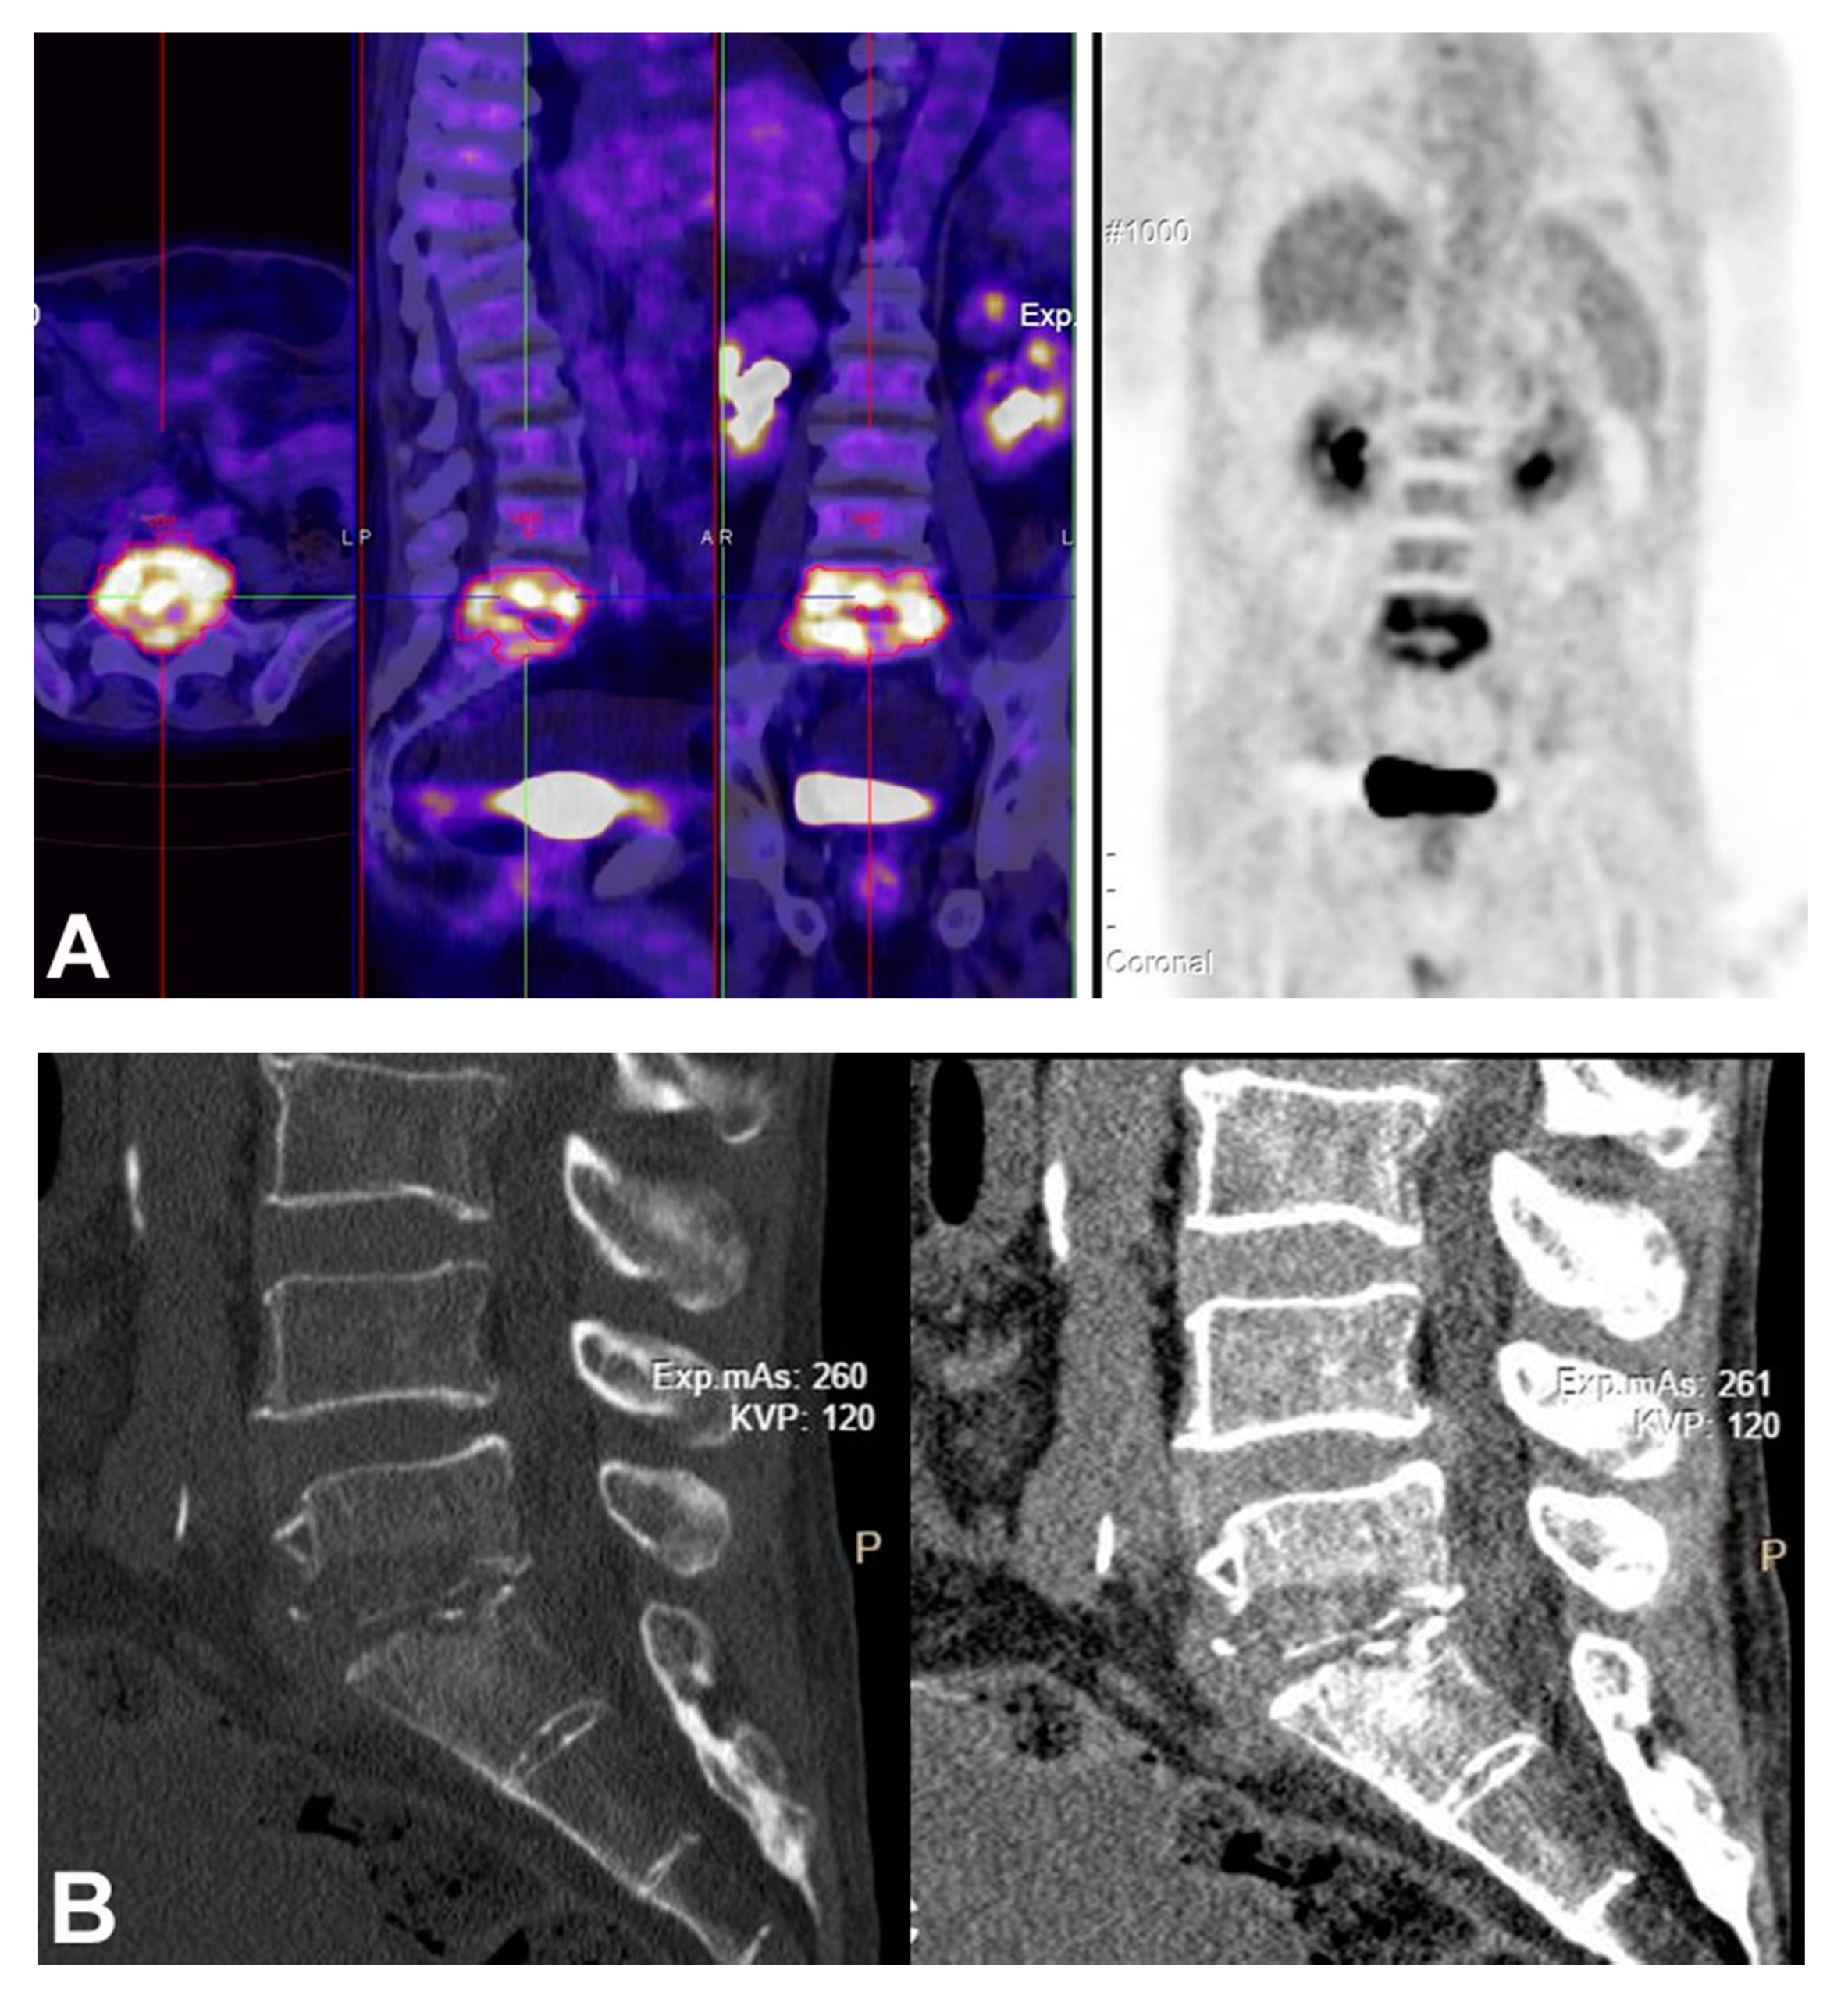

5. Diagnosis